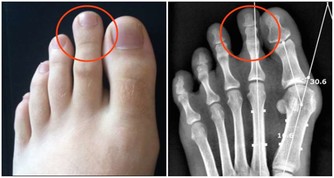

經常久坐的人,患上頸椎病的概率會更高。因為人體的骨連接需要足夠的黏液,來保證關節的正常使用。而久坐的人產生的黏液較少,會使骨關節變得乾燥,久而久之會引發頸椎病和關節炎。

此外,長時間保持一個姿勢不動,還會對頸椎動脈供血造成影響,並破壞人體正常生理彎曲,導致駝背和骨質增生。